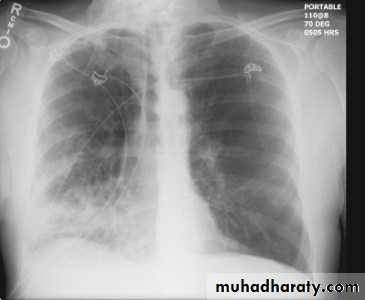

Left upper lobe collapse has distinctive features but can be challenging to identify on chest radiographs by the uninitiated.

Radiographic features

The left upper lobe collapses anteriorly becoming a thin sheet of tissue apposed to the anterior chest wall, and appears as a hazy or veiling opacity extending out from the hilum and fading out inferiorly . It thus reverses the normal slight increase in radiographic density seen as you move down the lung (due to increased thickness of the chest soft tissues).

Parts of the normal cardiomediastinal contour may also be obliterated where the left upper lobe, particularly the lingula abut the left heart border. The anterior parts of the aortic arch are also often obliterated from view.

In some cases the hyperexpanded superior segment of the left lower lobe insinuates itself between the left upper lobe and the superior mediastinum, sharply silhouetting the aortic arch and resulting in a lucency medially. This is known as the luftsichel sign.

The left hilum is also drawn upwards, resulting in an almost horizontal course of the left main bronchus and vertical course of the left lower lobe bronchus.

Non-specific signs indicating left sided atelectasis will also be present, including:

elevation of the hemidiaphragm

'peaked' or 'tented' hemidiaphragm: juxtaphrenic peak sign

crowding of the left sided ribs

shift of the mediastinum to the left

On lateral projections the left lower lobe is hyperexpanded and the oblique fissure displaced anteriorly. There is associated increase in the retrosternal opacity.